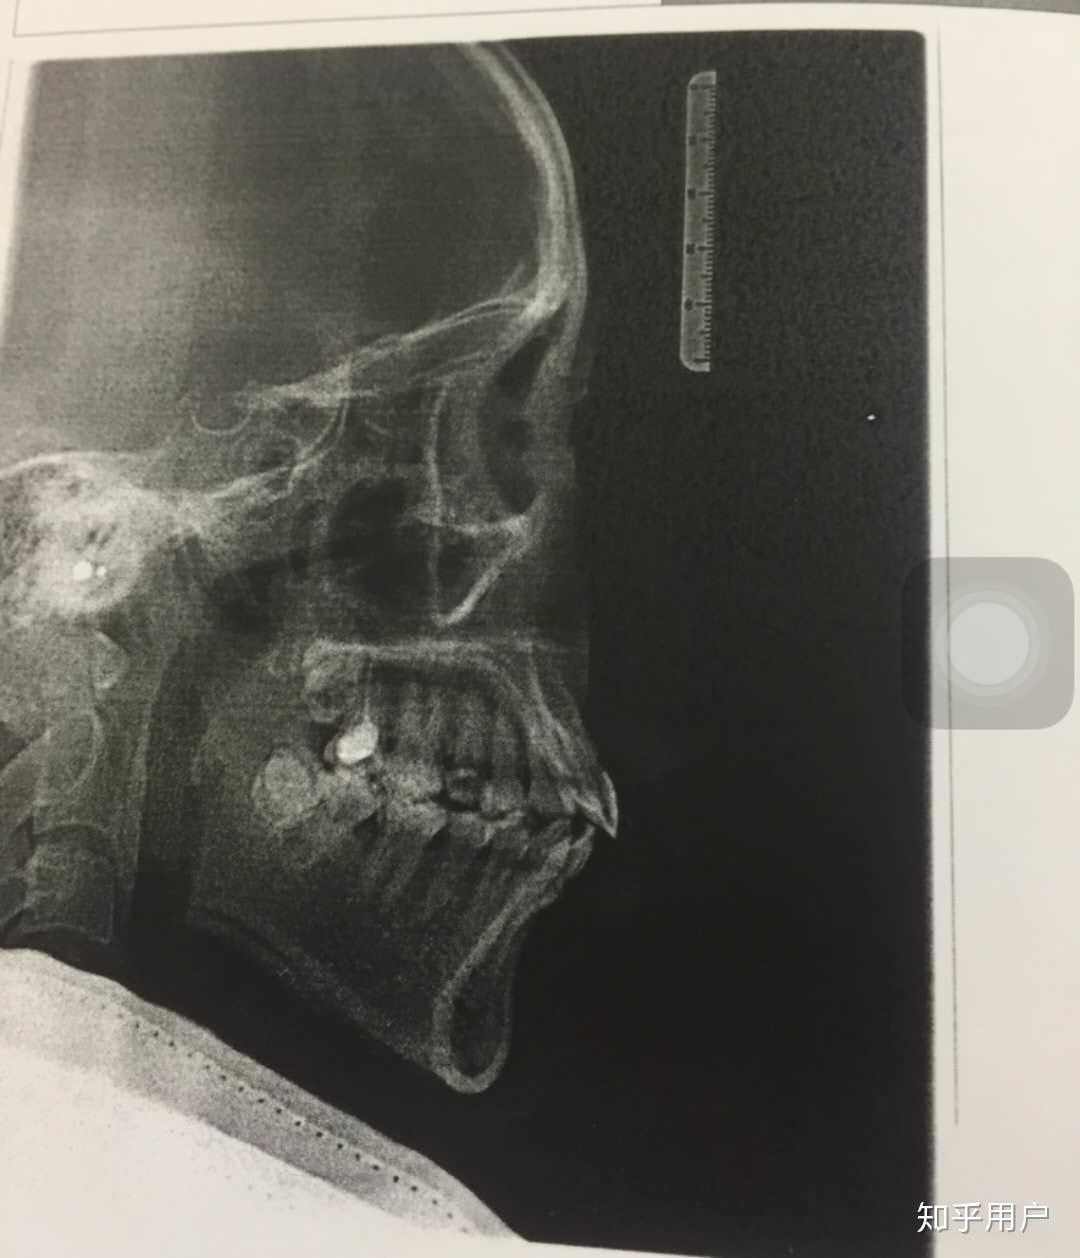

应要求上一个侧脸对比图

预警,X照有点吓人。

嘴突矫正以后,脸好像显得更平了

2016年4月X照